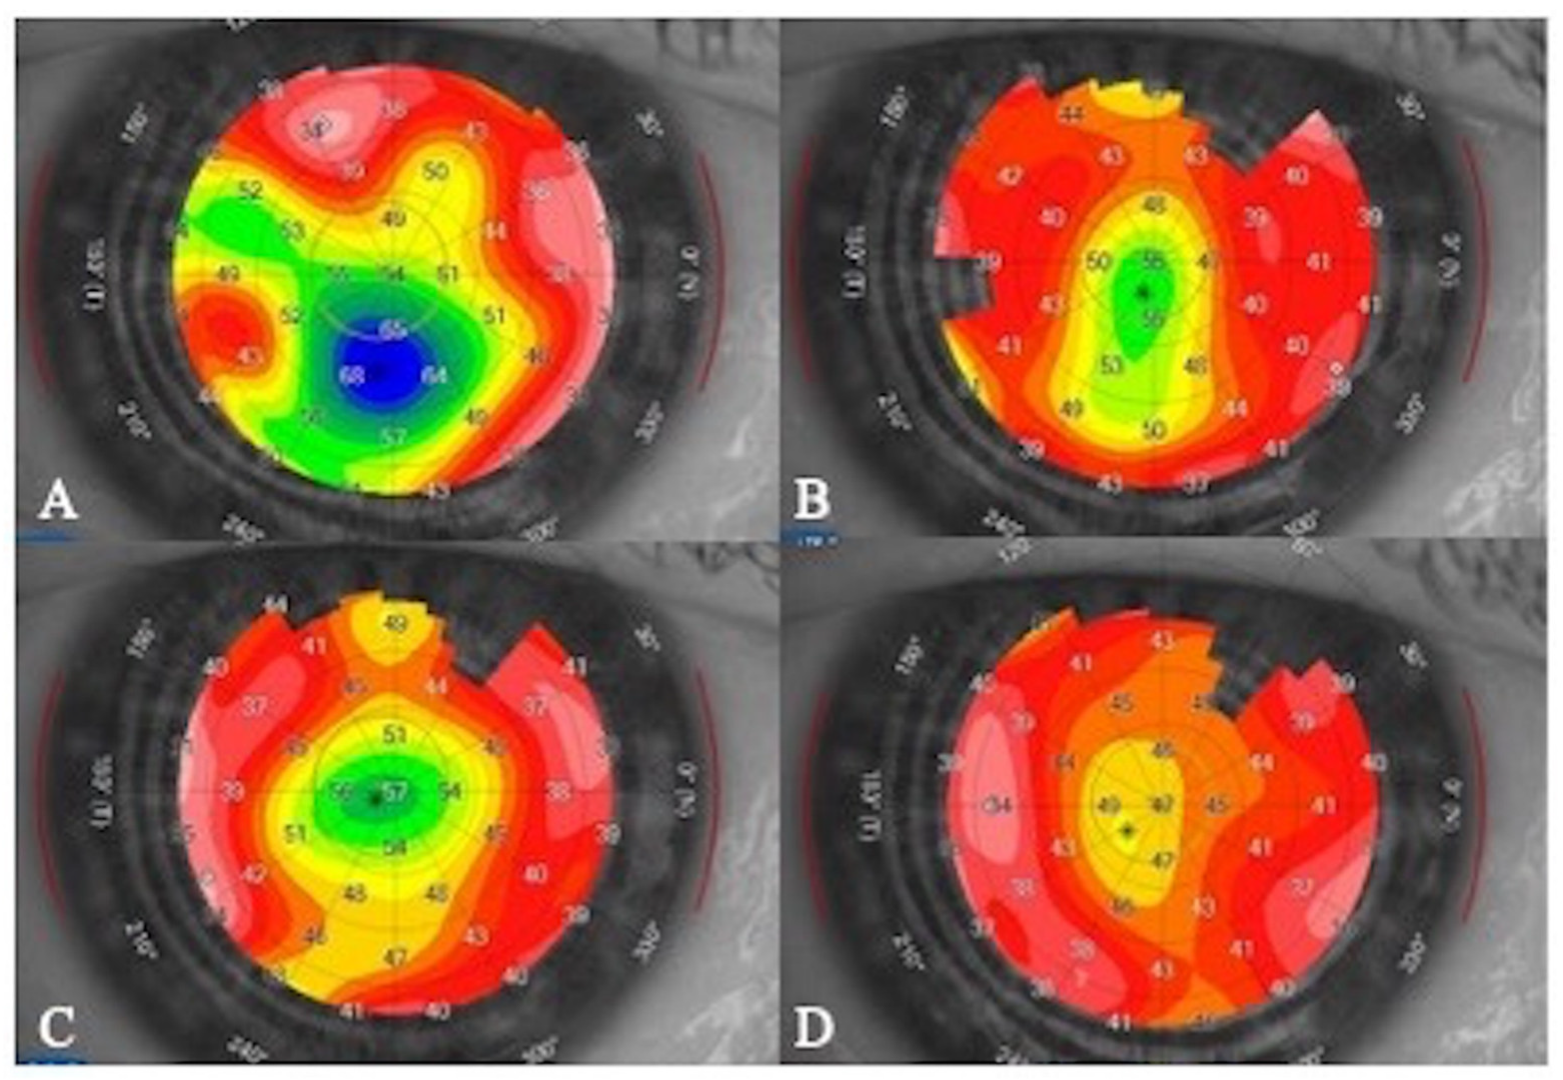

- Matsumiya, W.; Karaca, I.; Ghoraba, H.; Akhavanrezayat, A.; Mobasserian, A.; Hassan, M.; Regenold, J.; Yasar, C.; Liedtke, M.; Kitazawa, K.; et al. Structural changes of corneal epithelium in belantamab-associated superficial keratopathy using anterior segment optical coherence tomography. Am. J. Ophthalmol. Case Rep. 2021, 23, 101133. [Google Scholar] [CrossRef] [PubMed]